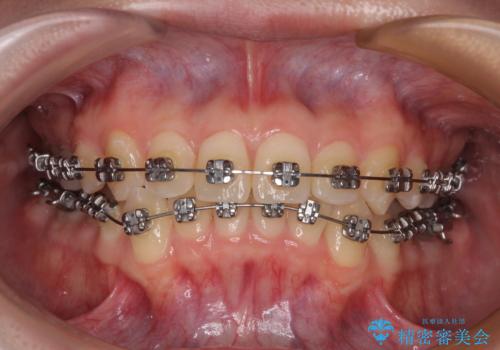

前歯のクロスバイト ギラギラのワイヤー装置で矯正治療

- 矯正装置

- メタルブラケット

- 治療期間

- 1年3ヶ月

クロスバイトが改善する際は、前歯しか接触しないため、痛みがあったり食事が取りにくかったりと、不便な時期がありますが、1年強の短期間で無事に治療を終えることができました。